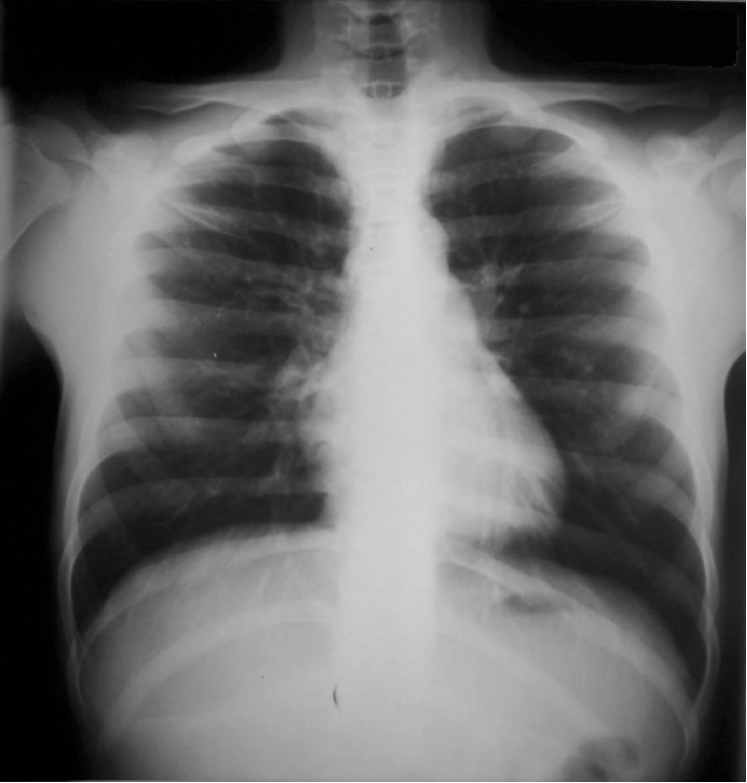

Refer to caption

(a) P-A

(b) Lateral

(c) Lordotic

(d) A-P supine

(e) A-P

(f) P-A

(g) Lateral

(h) Lordotic

(i) A-P supine

(j) A-P

Figure 2: Common chest x-ray projections.

The projection information is highly relevant for diagnosis. For example, AP views, which are commonly used in pediatric patients, show an enlarged heart silhouette (Fig. 2(j)) that should not be interpreted as cardiomegaly, but merely the expected large-depth ratio of reversed organ observation (Fig. 3). Another illustrative example is the distinct pattern that pleural effusions have in the standing position (Fig. 4(a)), in which a typical meniscus sign is commonly found as opposed to decubit projections (Fig. 4(b)). Given that the number of different projections is unbalanced (for instance, PA followed by lateral projections typically comprise the majority of chest x-rays), there is the risk that none of the other projections will have sufficient instances with which to train models capable of discriminating pathological from non-pathological patterns in the context of the projection.

There are particular radiological landmarks that differentiate projections, which radiologists are trained to identify. For instance, in the case of PA projections, these landmarks are the presence of air in the gastric chamber and the scapulae projected outside the lung fields. Although these features can be learned, models trained in unbalanced datasets with a poor representation for different projections may not have sufficient instances to properly learn those patterns. An illustrative example is when the heart enlargement in AP projections is attributable only to the effect of the projection, while the trained model erroneously predicts cardiomegaly.